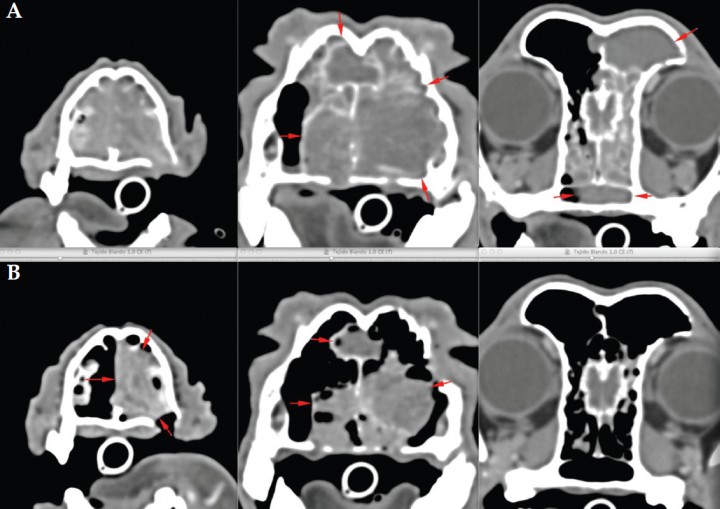

Se describe el caso clínico de una perra mestiza, castrada, de 11 años, con estridor respiratorio y epistaxis de varias semanas de evolución. En una tomografía computarizada (TC) se observó una masa que ocupaba la cavidad nasal izquierda e invadía parte de la derecha, con lisis de los huesos palatino, lacrimal izquierdo, maxilar y senos frontales, sin invasión de la lámina cribosa (estadio III, clasificación de Adams). Tras la biopsia se diagnosticó como adenocarcinoma nasal. El tumor se trató durante 5 meses con toceranib fosfato (2,7 mg/kg en protocolo de lunes-miércoles-viernes) (Palladia®, Zoetis, Madrid) y firocoxib (5 mg/kg martes-jueves-sábado; Previcox®, Merial Laboratorios, Barcelona), y aunque los propietarios observaron un beneficio clínico por mejora de los signos clínicos, la TC de control mostró enfermedad progresiva (Fig. 1), por lo que fue remitida para tratamiento de radioterapia.

<p>Imagen en TC post-contraste en plano transversal y ventana de tejido blando. Se aprecia una masa que ocupa la cavidad nasal izquierda e invade parte de la derecha, con lisis de los huesos palatino, lacrimal izquierdo, maxilar y senos frontales, sin invasión de la lámina cribosa.</p>

Imagen en TC post-contraste en plano transversal y ventana de tejido blando. Se aprecia una masa que ocupa la cavidad nasal izquierda e invade parte de la derecha, con lisis de los huesos palatino, lacrimal izquierdo, maxilar y senos frontales, sin invasión de la lámina cribosa.

<p>Imagen en TC post-contraste en plano transversal y ventana de tejido blando. (A) Al inicio del tratamiento con radioterapia. (B) A los 3 meses del tratamiento, donde se observa una marcada reducción del volumen tumoral.</p>

Imagen en TC post-contraste en plano transversal y ventana de tejido blando. (A) Al inicio del tratamiento con radioterapia. (B) A los 3 meses del tratamiento, donde se observa una marcada reducción del volumen tumoral.